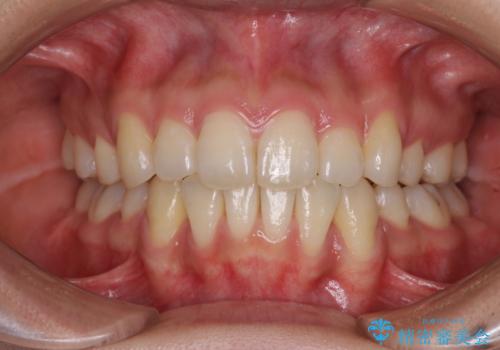

- 口元のデコボコと深い咬み合わせ(ディープバイト)を気にして来院された患者様です。

インビザラインによる上下歯列の拡大と、IPR(歯と歯の間を削る)にるスペースの獲得により、口元のデコボコとディープバイトを改善することとしました。